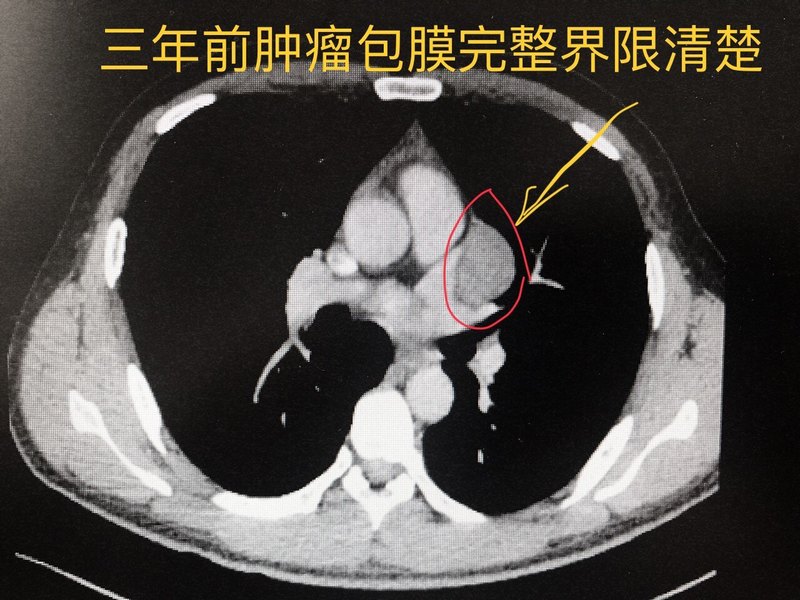

3年前收治的一例胸腺瘤合并重癥肌無力男性37歲患者,因肌無力比較重轉內科控制重癥肌無力癥狀。后患者出院一直沒有手術。三年來間斷隨訪。前天因胸疼急診入院復診,發(fā)現(xiàn)腫瘤已顯著增大。 原來基本上包膜完整,微創(chuàng)胸腔鏡可以摘除,手術風險相對較小;現(xiàn)在侵潤心包大血管,需要胸骨劈開切除腫瘤,手術風險更大更復雜了。 胸腺瘤確診后還是要盡早做手術。